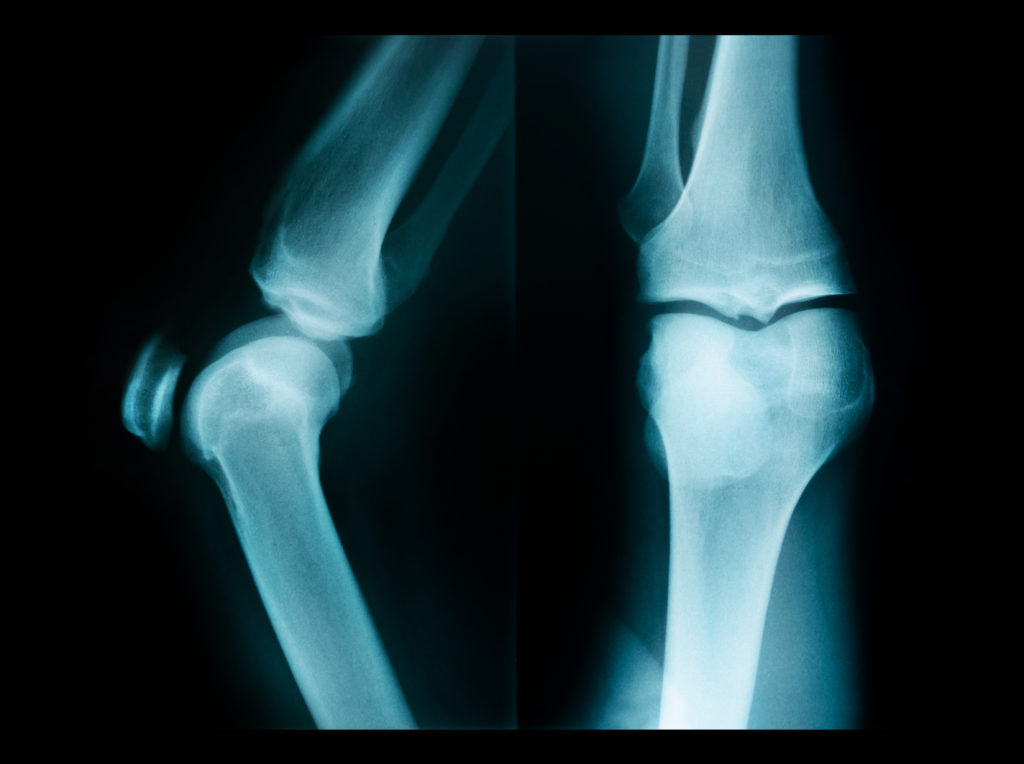

Read more.What to Expect with a MAKO Knee Surgeon in Beverly Hills, CA

Read more.Mako Partial Knee Replacement Surgery

For some, the thought of living with their knee discomfort may seem more comfortable than the pain of a mako

Read more.Mako Total Knee Replacement Surgery

Completely replacing a patient’s knee is a serious decision requiring expert surgical precision. With the advanced technology of the Mako

Read more.Types of Knee Replacement Surgery Los Angeles & Beverly Hills

The knee joint is extremely strong, and provides support and mobility. But because of the weight it bears, knee injuries